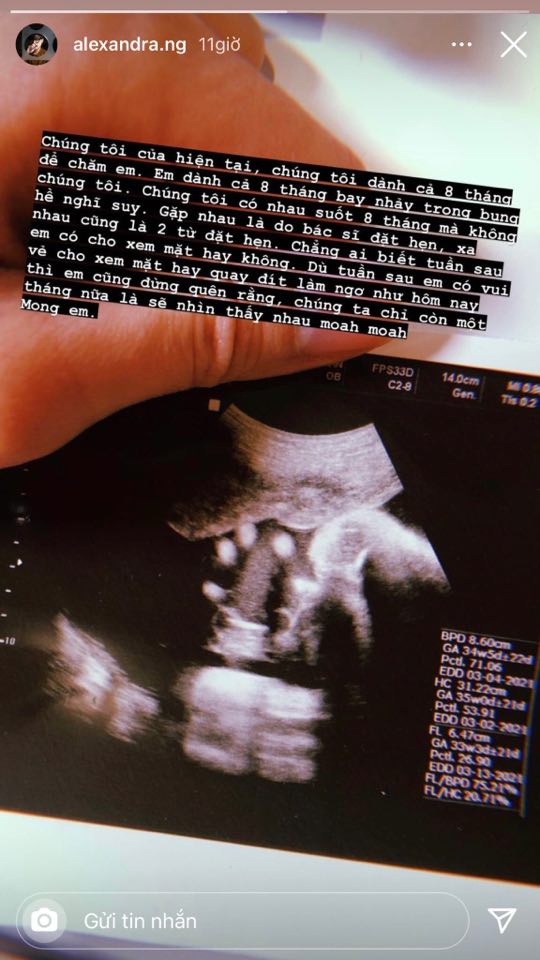

Trên trang cá nhân, Alex Nguyễn - người yêu đồng giới của An Nguy mới đây đã chia sẻ hình ảnh chụp siêu âm thai nhi.

Đi kèm với bức hình, Alex Nguyễn không quên để lại dòng trạng thái dài tiết lộ chuyện chỉ còn 1 tháng nữa em bé sẽ chào đời: "Chúng tôi của hiện tại, chúng tôi dành cả 8 tháng để chăm em. Em dành cả 8 tháng bay nhảy trong bụng chúng tôi. Chúng tôi có nhau suốt 8 tháng mà không hề nghĩ suy", Alex Nguyễn nhắn nhủ.

Người yêu đồng giới của An Nguy chia sẻ thêm: "Gặp nhau là do bác sĩ đặt hẹn, xa nhau cũng là 2 từ đặt hẹn. Chẳng ai biết tuần sau em có cho xem mặt hay không. Dù tuần sau em có vui vẻ cho xem mặt hay quay đít làm ngơ như hôm nay thì em cũng đừng quên rằng, chúng ta chỉ còn một tháng nữa là sẽ nhìn thấy nhau. Mong em".